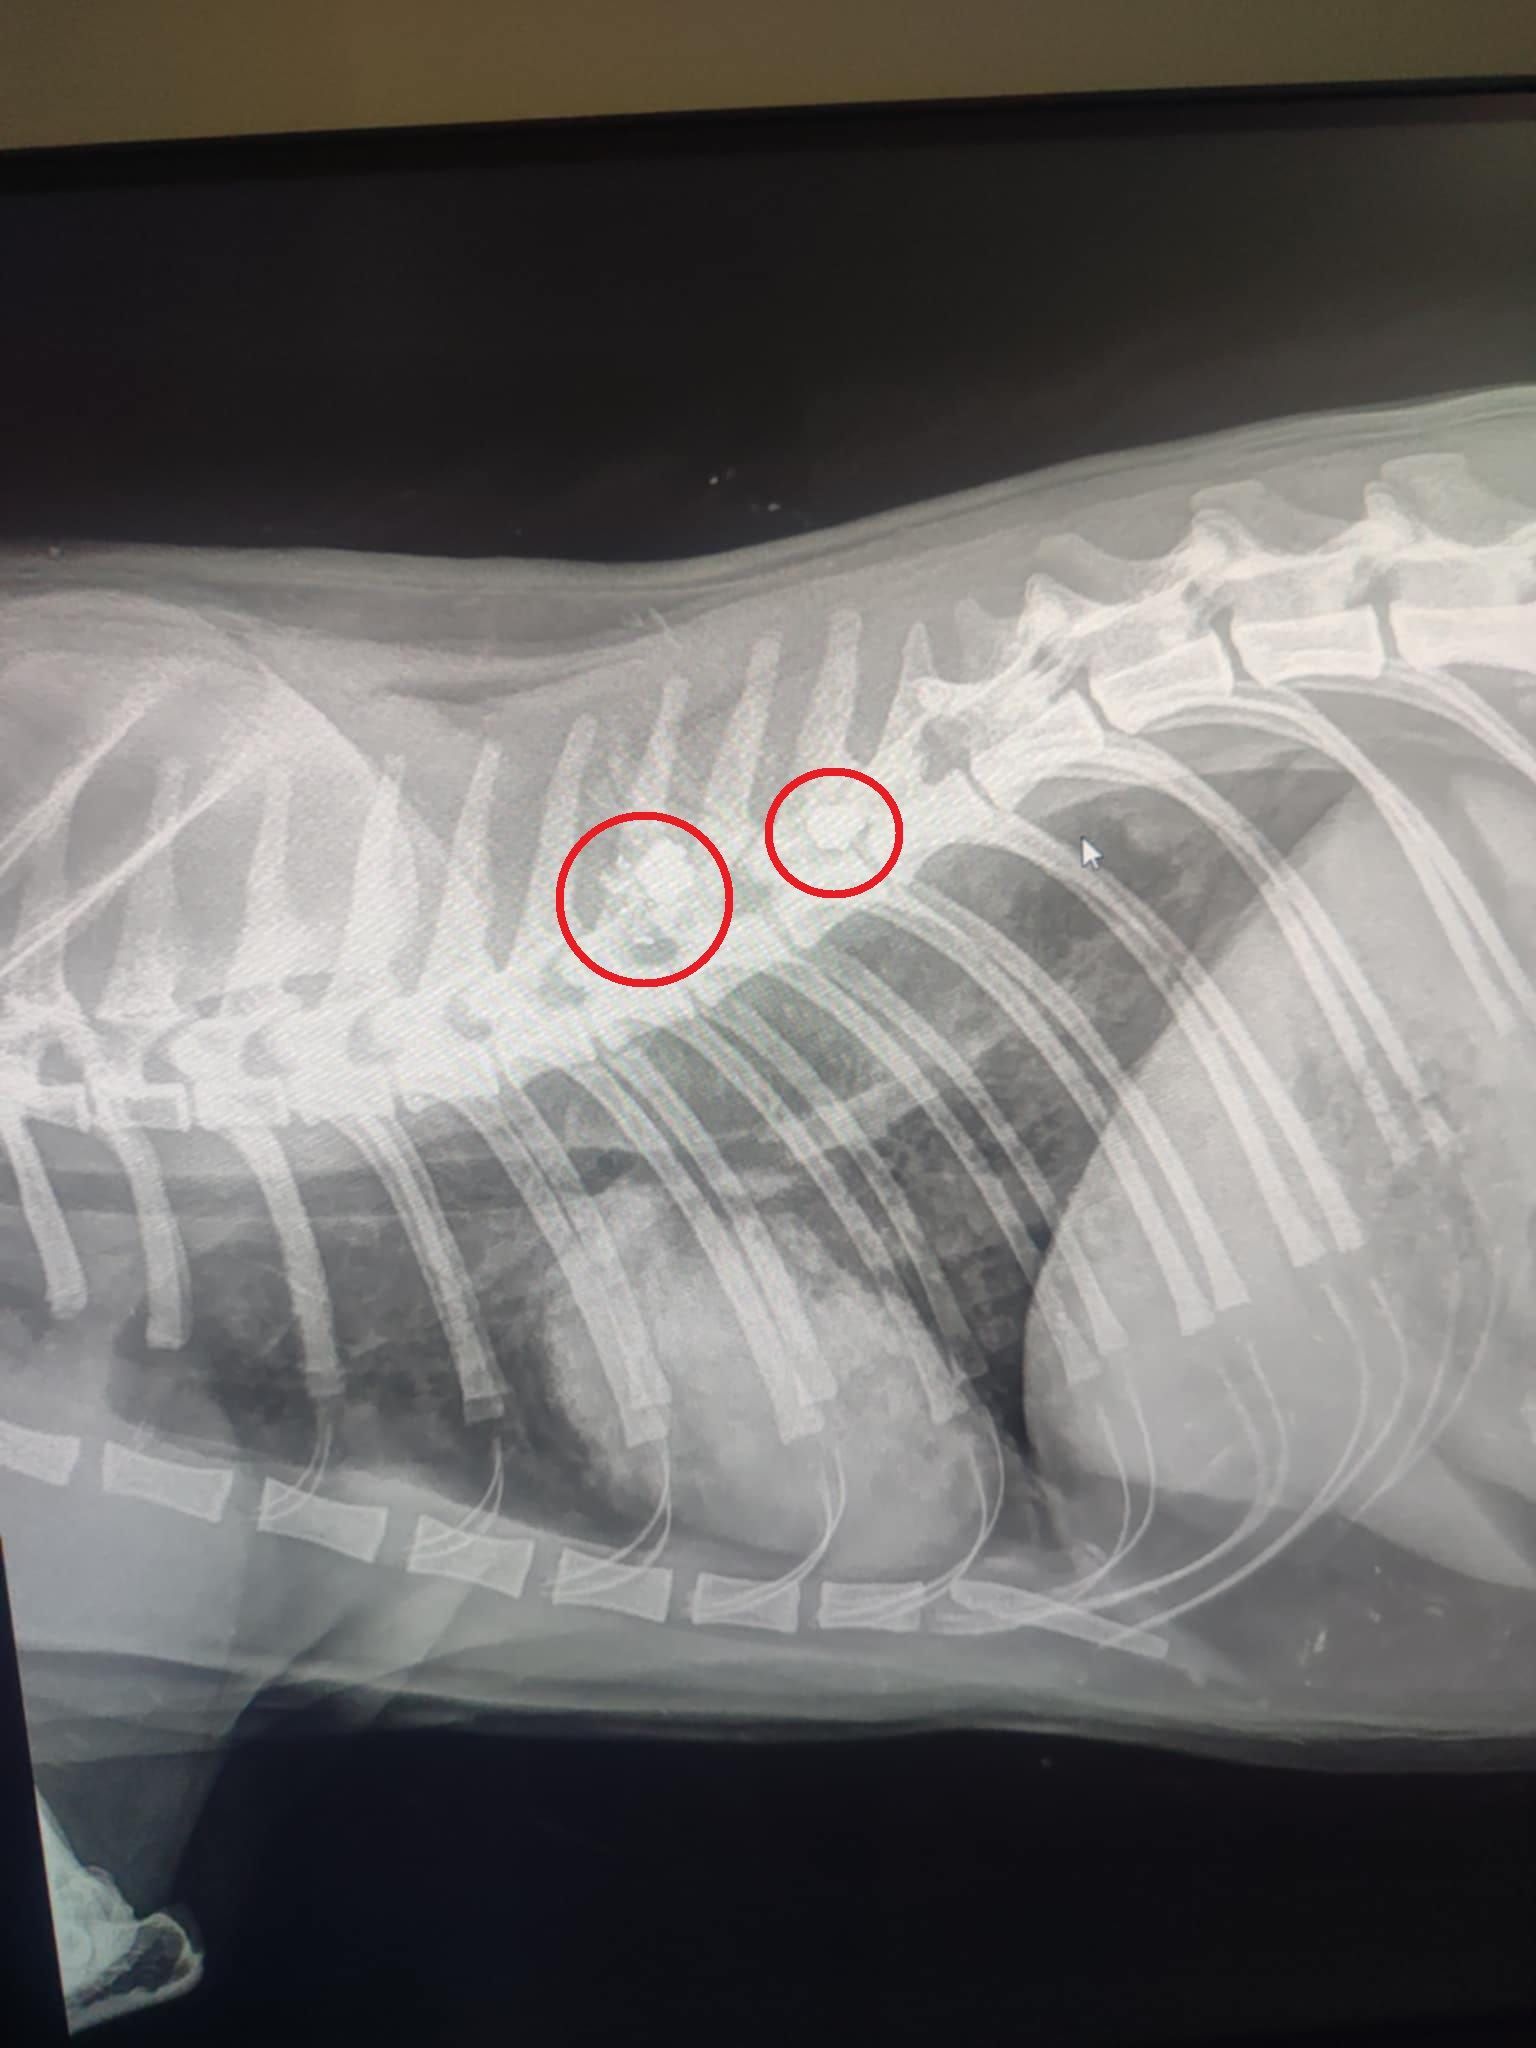

Το ζώο, όπως έδειξαν οι ακτινογραφίες, είχε πυροβοληθεί με αεροβόλο δύο φορές. Το ένα σφαιρίδιο είχε καρφωθεί στην σπονδυλική του στήλη και αν δεν είχε πάει επί τόπου ο εθελοντής διασώστης Κώστας Μαμασούλας, ώστε και να το πιάσει και να το μεταφέρει σε κτηνιατρική κλινική, η γάτα θα ήταν ήδη νεκρή και θα είχε μαρτυρικό θάνατο…

Οι πιθανότητες να περπατήσει είναι λιγες, ωστόσο αποφασίστηκε να κάνει το χειρουργείο και να του δώσουμε έστω αυτή την μικρή πιθανότητα ώστε να βγει η σφαίρα που είχε σφηνώσει στην σπονδυλική στήλη και να αποσυμπιεστεί. Τώρα το μόνο που μας μένει είναι να περιμένουμε, καθώς είναι πολύ δύσκολο ζώο και καθόλου συνεργάσιμο.».